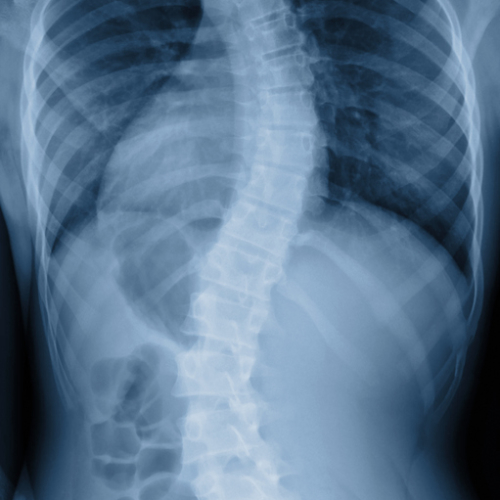

Explaining The Five Types Of Scoliosis Curves

Scoliosis Xray Replacement Scoliosis Monitoring Using Standing MRI Scoliosis School Accommodations Miss a lot of class time if surgery is needed; Miss a lot of class time if surgery is needed; Need extra time to complete. Feel embarrassed about wearing a brace; Discover helpful techniques, accommodations, and. Congenital scoliosis, the least common form, is present at birth, and caused by a failure of the vertebrae to form normally. Feel embarrassed about. Scoliosis School Accommodations.